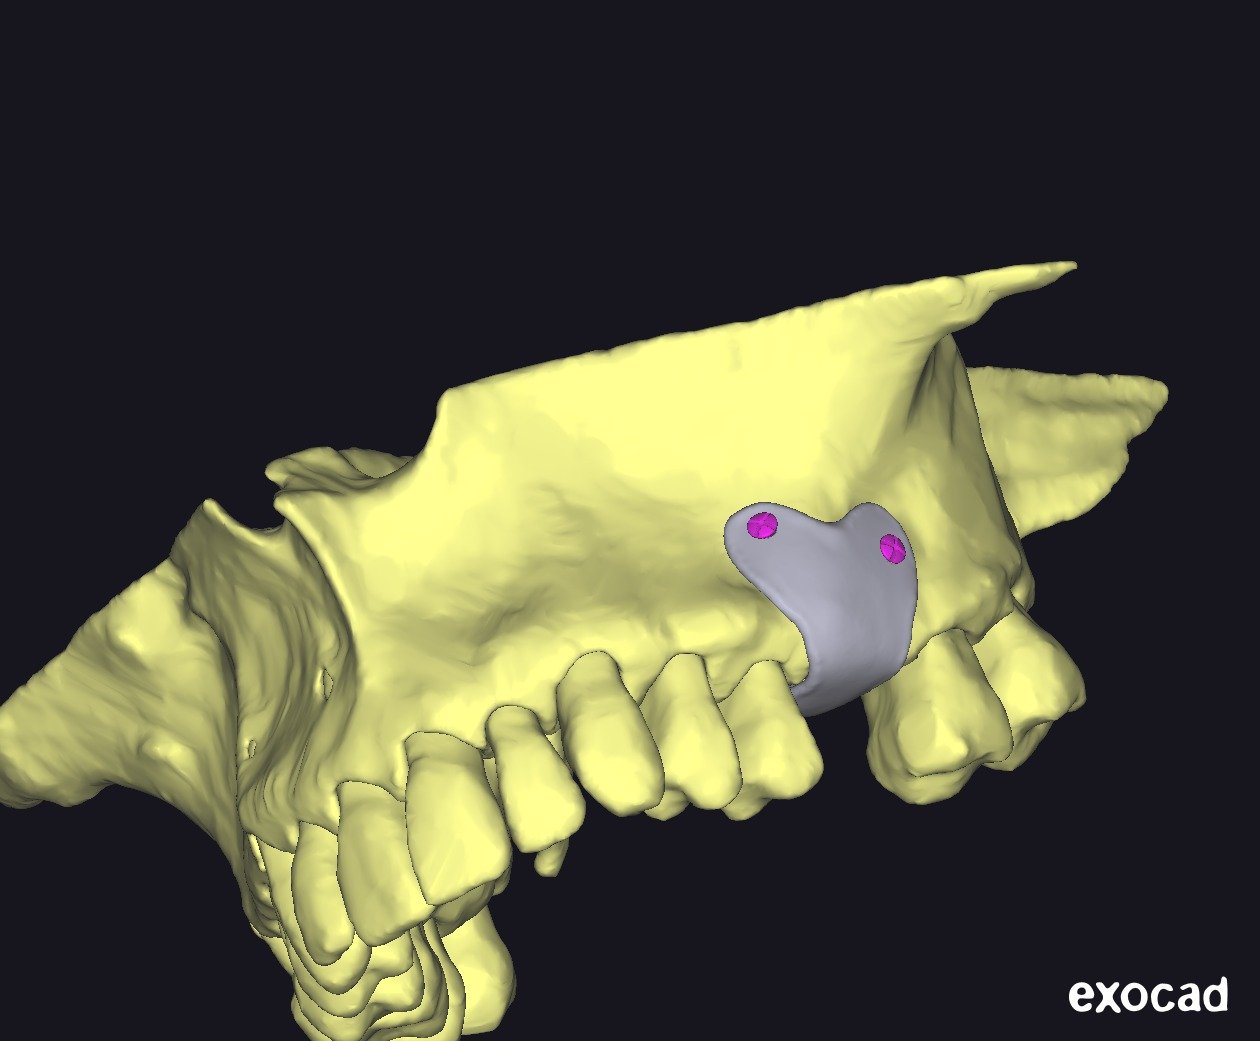

• Exoplan / Exocad: diseño digital aplicado a la regeneración.

• Concepto de barrera personalizada.

• Principios de diseño biomecánico.

• Espesor, extensión y bordes de la barrera.

• Diseño pasivo y adaptación milimétrica.

• Planificación de tornillos de fijación:

• Número

• Posición

• Angulación

• Relación barrera hueso – tejidos blandos.